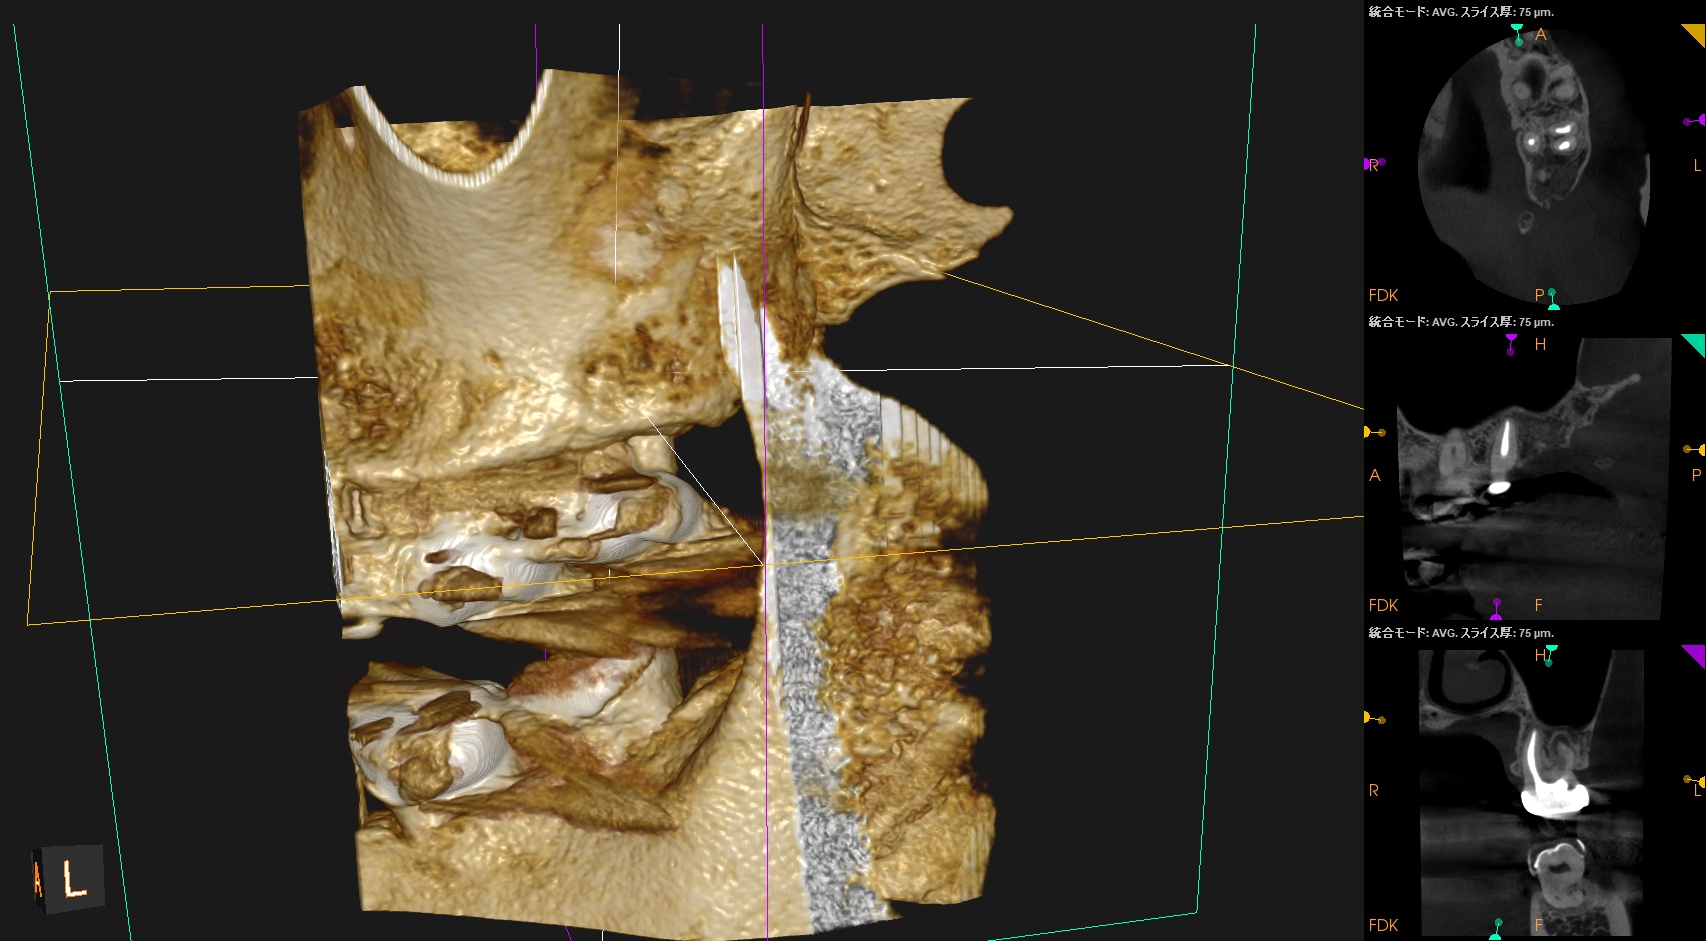

左上7番のMB,DBをApicoectomyしたと言う珍しい?ケースだ。

#15 MB,DB Apicoectomy 1yr recall(2026.1.15)

術前の根尖病変、術直後の歯槽骨の欠損は完治した。

ということで経過観察もこの日で終了した。

長い間、お疲れ様でした。